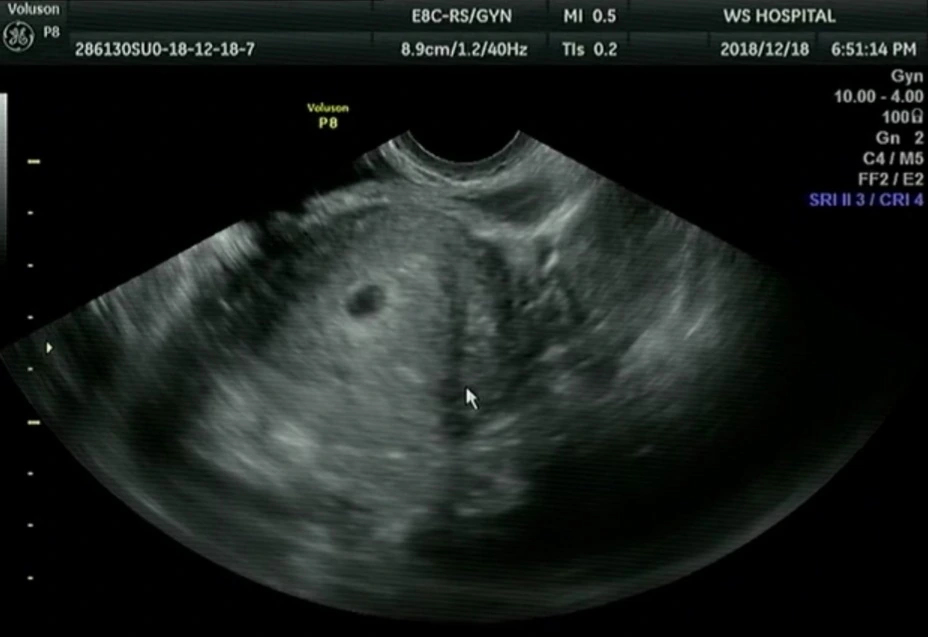

초음파로 보니 아기집도 더 커졌고 난황도 생겼고 그 전에는 안 보이던 하얀 아기 형상도 보였다.

"6주 차예요. 근데 아기 심장 소리가 안 들리네요."

청천벽력이었다. 다음 주에는 아기 심장소리를 들을 수 있고 들어야만 한다는 의사의 말을 지난주에 들었던 터라 아기 심장소리가 안 들린다는 말에 억장이 무너졌다.

"아직 너무 작아서 안 들리는 걸 수도 있어요. 유산이 진행되고 있는 중이라서 안 들리는 걸 수도 있고요. 다음 주 월요일 아침에 검사하러 오세요. 다음 주 월요일도 심장이 안 뛰면 안타깝지만 유산 확정입니다. 다음 주에는 꼭 남편분과 같이 오세요."

오늘 병원에서 본 초음파에는 더 커진 듯한 아기와 전에는 못 봤던 꼬리같이 생긴 탯줄도 있었는데.. 심장이 여전히 뛰질 않았다.

의사는 담담하게 계류유산을 선언하고 하루라도 빨리 소파술을 하라고 말했다.